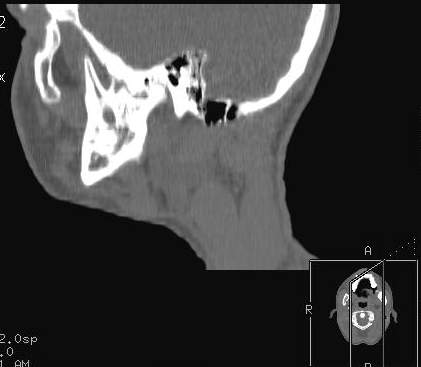

Пациент В., 13 лет. Диагноз: Костный анкилоз левого височно-нижнечелюстного сустава (ВНЧС), левосторонняя микрогения. Болеет с 2-х летнего возраста. Возможная причина развития анкилоза – воспалительный процесс (в первые 1,5 года жизни часто болел простудными заболеваниями, травму родители отрицают). В 3 и 5 лет проводилась редрессация – безуспешно.Прилагаются: ортопантомограмма, кадры СКТ с 3Д реконструкцией. Вопросы: определение тактики лечения – вид и сроки реконструктивно-пластической операции (этапов операции), а именно – неоартропластики и устранения микрогении, медикаментозная терапия в до- и послеоперационный период, ортодонтическое лечение.